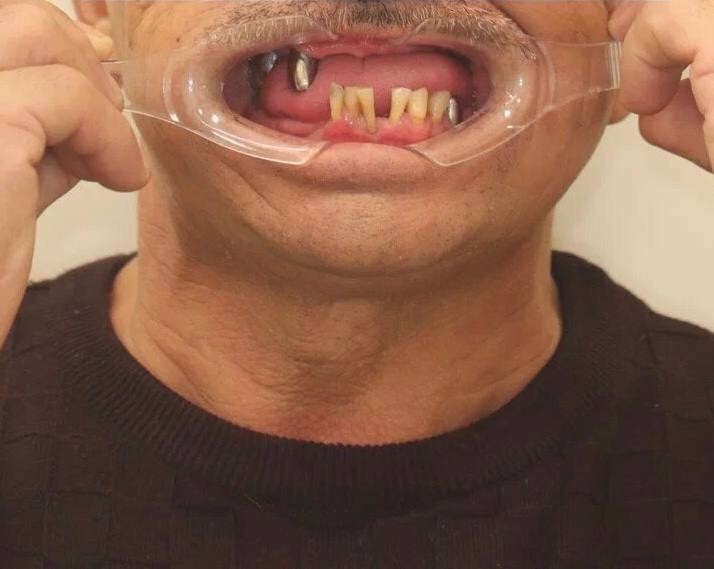

Одномоментная имплантация

Пациент 60 лет обратился с жалобой на неудовлетворительный эстетический вид старых коронок. После их снятия 3 зуба не подлежат протезированию. Проведено удаление с одномоментной установкой 2 дентальных имплантатов «Nobel Biocare» и изготовлением временного мостовидного протеза. Через 3 месяца проведено протезирование циркониевым мостовидным протезом с опорой на имплантаты.

Имплантация All-on-4

Пациентка, 65 лет обратилась с целью протезирования. На верхней челюсти изготовлен полностью съемный постоянный протез, а на нижней челюсти проведено удаление всех зубов (хронический пародонтит IV степени тяжести) и одномоментно установлено 4 дентальных имплантата «Nobel Biocare» по концепции «Всё-на-4 (All-in-4)» и временные мосты на имплантатах. Спустя 2,5 месяца проведена замена временных зубов на металлокерамический мост из 12 единиц с опорой на 4 имплантата.